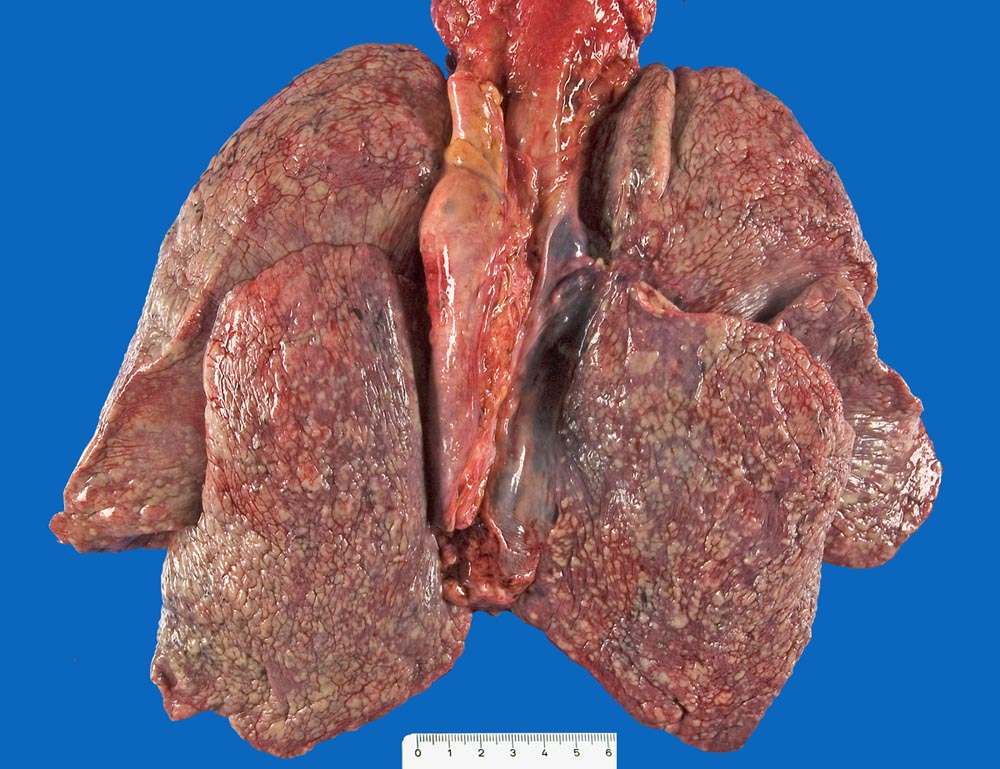

Mammakarzinom: Pleurakarzinose

Pleura

Diffuse knotige Tumordurchsetzung der Pleura visceralis aller Lungenlappen.

Skelettmetastasen in der Wirbelsäule von zervikal bis sakral sowie des Sternums mit Verdrängung der Hämatopoese. Minimale Restanteile des hämatopoetisch aktiven Knochenmarks (Thrombopenie laut klinischen Angaben). Metastasenleber mit sekundären ischämischen Infarkten. Hämangiosis carcinomatosa des Myokards. Lymphangiosis carcinomatosa der Lungen, des Myokards und des Perikards. Nervenscheideninfiltration des Tumors in der Pleura. Pleurakarzinose (Pleuraerguss rechts: 750ml).

Mässig differenziertes invasiv duktales Mammakarzinom (pT2 pN1 G2). Ablatio mammae vor 14 Jahren. Brustwandrezidiv und Radiotherapie (50 Gy) vor 6 Jahren.